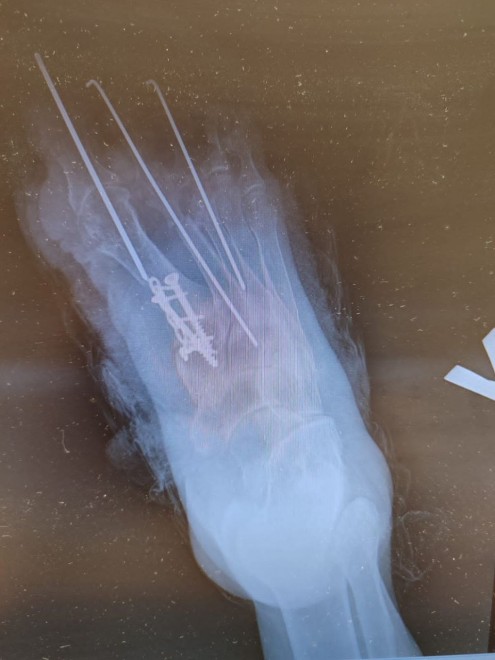

В пресс-службе больницы рассказали, что у женщины была приобретенная вальгусная деформация первого пальца и молоткообразные изменения второго и третьего пальцев. Из-за этого она не могла нормально ходить, долго стоять, ее мучили боли. Кроме того, красноярка не могла выбрать подходящую обувь.

По словам оперировавшего хирурга-травматолога-ортопеда Виталия Шапкина, операция длилась около 1,5 часов:Изначально женщина проходила консервативное лечение, но оно не давало результатов. Единственным выходом для нее стала операция. Пациентка консультировалась со многими хирургами, но никто не соглашался на операцию. В итоге на помощь женщине пришли травматологи БСМП.

Теперь после такой операции красноярке требуется длительное восстановление. Сейчас женщина ходит в специальной обуви. Через 3 месяца ей предстоит операция на второй стопе с меньшей деформацией.«Для возвращения стопы в анатомически правильное положение нами была проведена кропотливая работа. Мы достигли желаемого результата, и через неделю после операции пациентка была выписана домой».